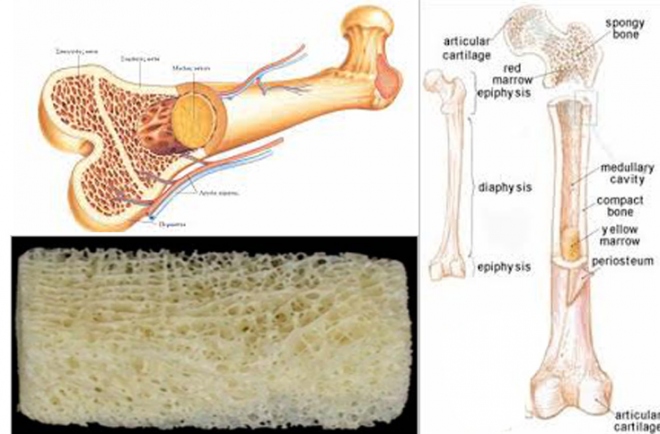

Το κάταγμα του μηριαίου είναι διακοπή της συνεχείας του μηριαίου οστού, που είναι όπως έχει αναφερθεί ένα αυλοειδές οστούν.

Η περιοχή των τροχαντήρων και των μηριαίων κονδύλων έχει κατασκευή από σπογγώδες οστούν.

Μέσα στον αυλό του μηριαίου στην παιδική μέχρι την εφηβική ηλικία, υπάρχει μυελός των οστών, που υποβοηθάει την αιμοποίηση. Στους ενήλικες μυελός υπάρχει μόνο στα σπογγώδη οστά. Ο αυλός του μηριαίου, ο μυελός, αντικαθίσταται από λίπος.

Μέσα στον αυλό του μηριαίου στην παιδική μέχρι την εφηβική ηλικία, υπάρχει μυελός των οστών, που υποβοηθάει την αιμοποίηση. Στους ενήλικες μυελός υπάρχει μόνο στα σπογγώδη οστά. Ο αυλός του μηριαίου, ο μυελός, αντικαθίσταται από λίπος.

Ο φλοιός των αυλοειδών οστών είναι πολύ ισχυρός και γι΄ αυτό τα κατάγματα στα αυλοειδή οστά, είναι αποτέλεσμα μεγάλης βίας.